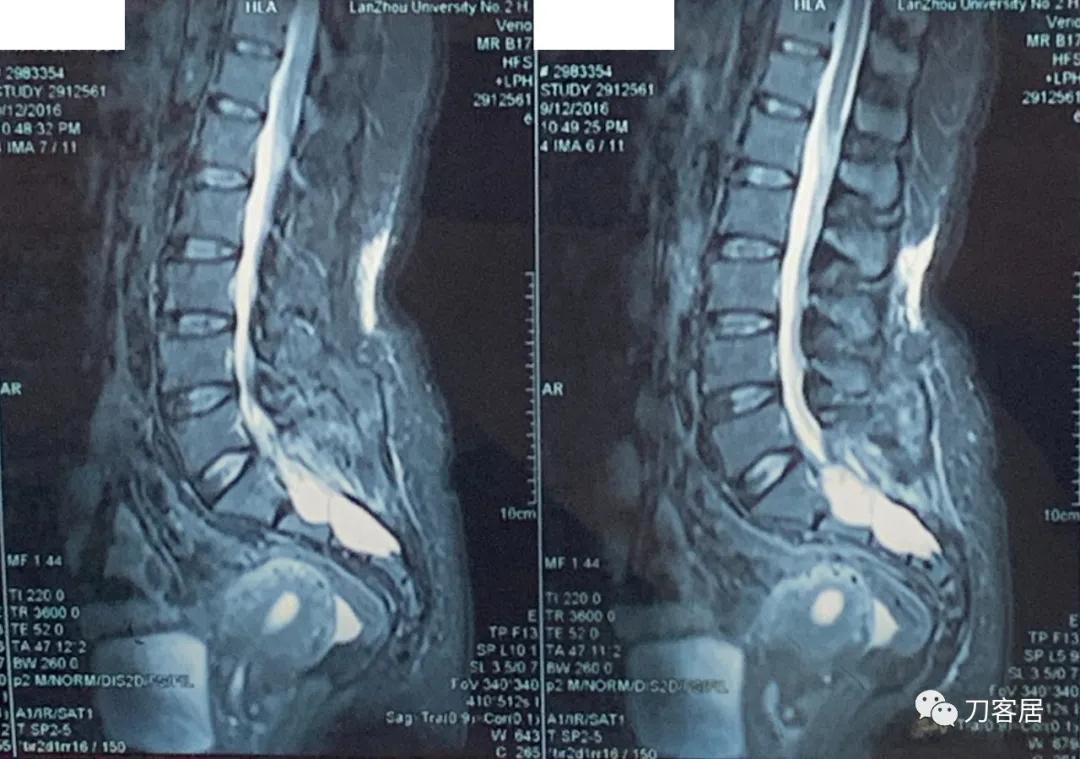

20160217患者骶管囊肿术前的腰骶椎磁共振

20160912患者骶管囊肿术后的腰骶椎磁共振